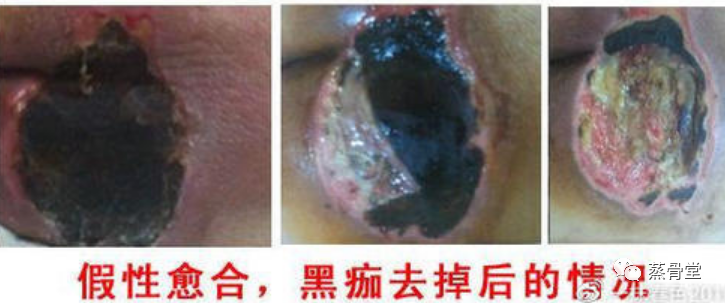

重点科普一:黑痂型褥疮——*具迷惑性的“假性愈合”,越忽视越危险

在所有褥疮类型中,黑痂型褥疮*容易让人陷入误区,很多家属看到创面结痂,就以为“快要好了”,殊不知,这正是*危险的“假性愈合”,

黑痂之下,“别有洞天”很可能早已“烂入深处”。

这里必须再次郑重提醒:褥疮结痂**不是好转的表现!很多人误以为“结痂就是伤口愈合”,但对于褥疮这种缺血缺氧性坏死创面来说,

结痂反而可能是“致命陷阱”。

黑痂就像一个“盖子”,将创面牢牢盖住,表面看起来愈合良好,但痂下很可能已经出现脓液、腐肉,肌肉层早已腐烂加深,形成“口小、

肚子大”的隐蔽溃烂——这种情况下,若不及时处理,褥疮会从三期直接恶化到四期,侵蚀肌肉、骨骼,后果不堪设想。

正确认识黑痂型褥疮的发展过程:当黑痂下方有脓液渗出时,说明痂下的肌肉层已经腐烂很深;只有当黑痂、腐肉完全脱落,创面

露出新鲜的红肉时,才是褥疮得到控制、向好发展的信号。请所有家属牢记:没有长不住的褥疮创口,只有用错的处理方法,一旦

发现黑痂型褥疮,切勿盲目等待痂皮脱落,必须及时采取科学方法处理,除腐肉、排出脓液,才能避免病情恶化。